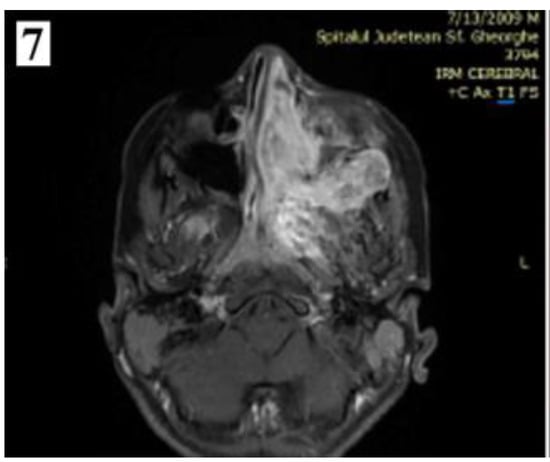

Figure 7.

Preoperative MRI of a stage IIC juvenile angiofibroma. The Holman-Miller sign (the anterior bowing of the posterior maxillary wall) on the CT scan (part 1).